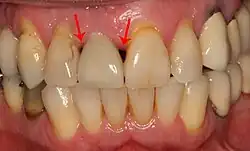

Потеря костной массы (периимплантит) на имплантатах более 7 лет у заядлого курильщика

Спад десны приводит к обнажению металлического абатмента под зубной коронкой.

Чёрные треугольники, вызванные потерей костной массы между имплантатами и естественными зубами